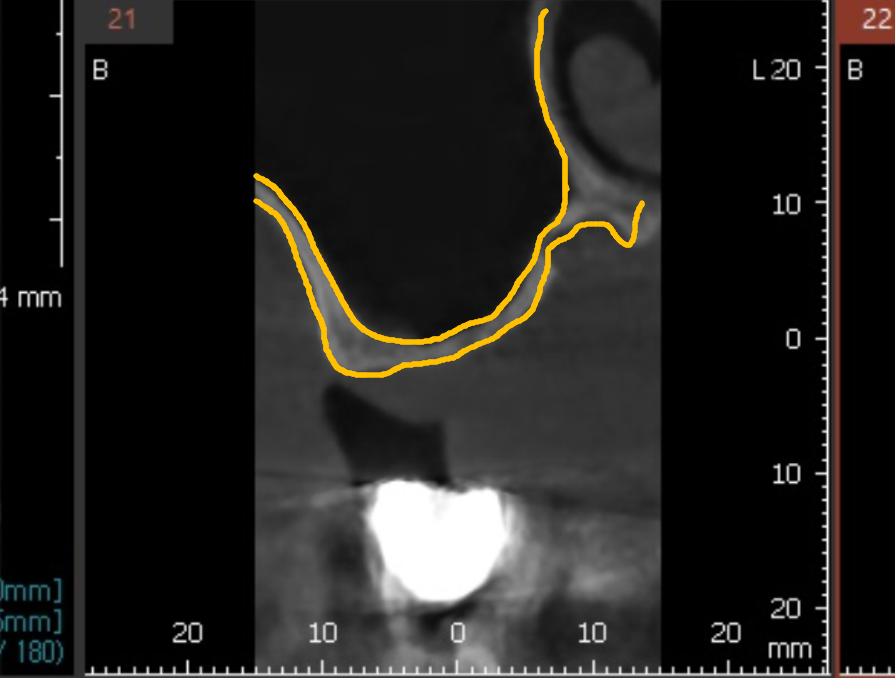

사진상에서 보면 이 부위가 상악동인데,

까맣게 보이는 이유는 안이 뻥~ 뚫려 있기 때문이죠.

그런데 이 환자분은 1.5mm밖에 남지 않은 상태였습니다.

CT도 같이 살펴볼게요.

노란색으로 표시한 잇몸뼈 부분,

눈으로 보기에도 굉장히 얇죠?